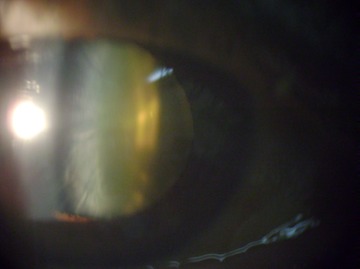

IMG 1158

Catarata Cortical Anterior por Retroiluminación